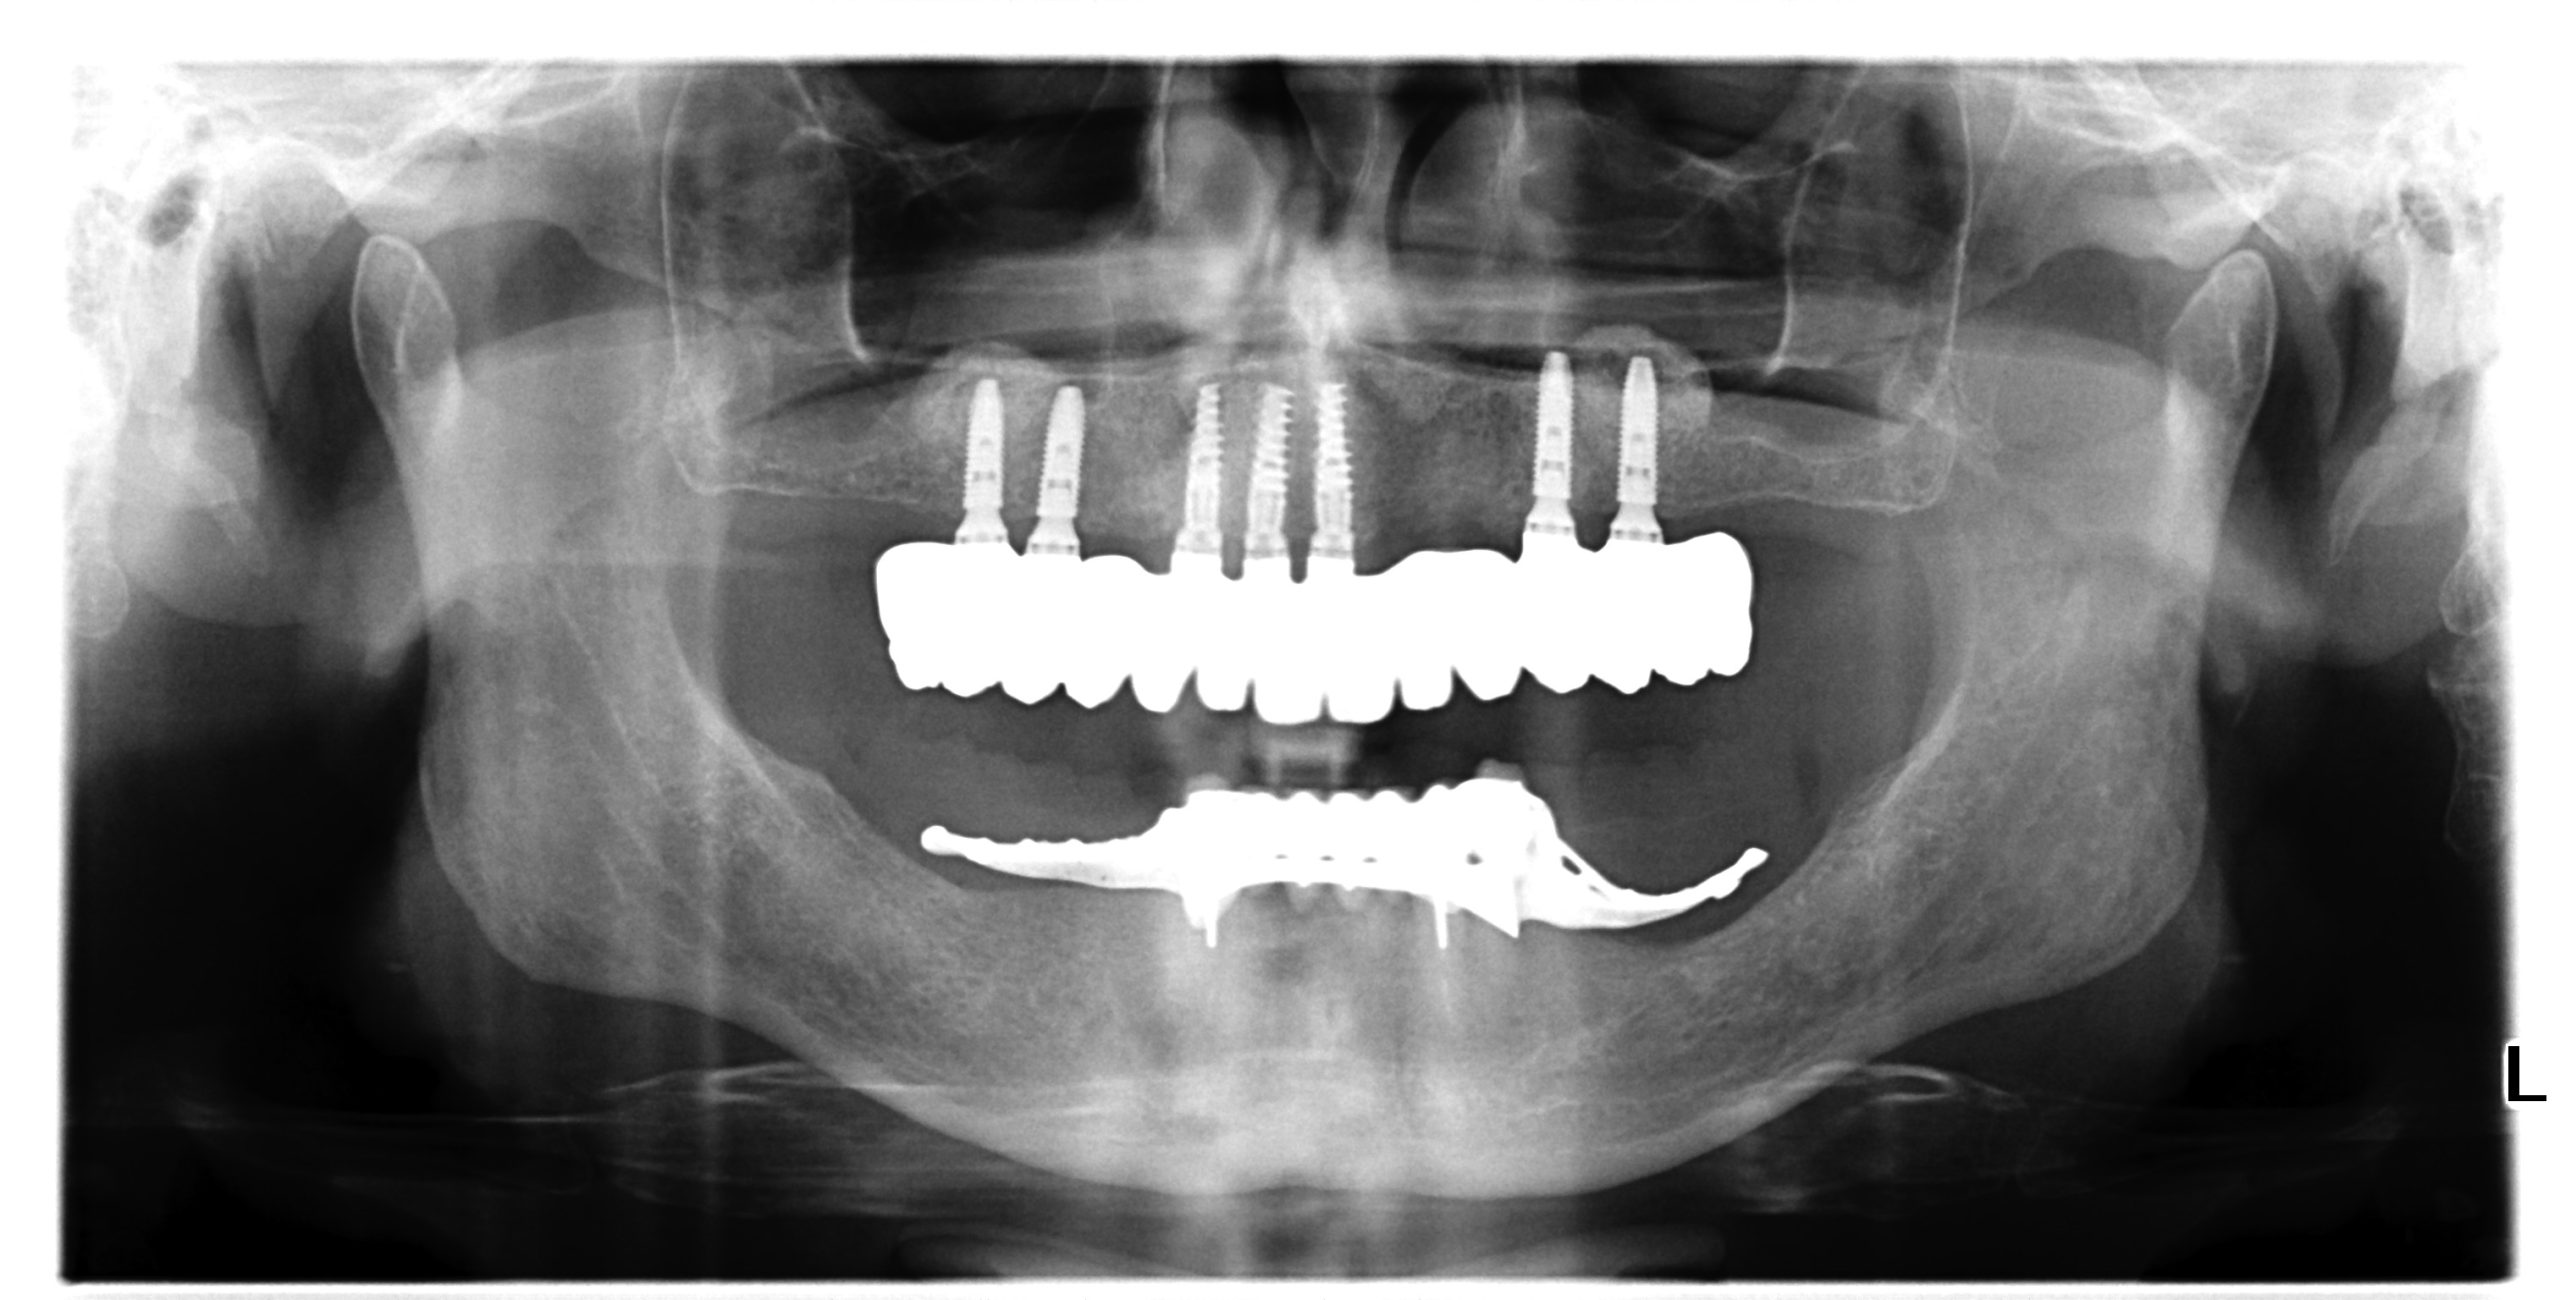

The use of CDP (Complete Digital Patient) as a basis for planning in a case of complete implant rehabilitation with a full arch in zirconia – ceramicised

Digital Patient

Total upper and lower rehabilitation using CDP technology as an analysis and planning tool